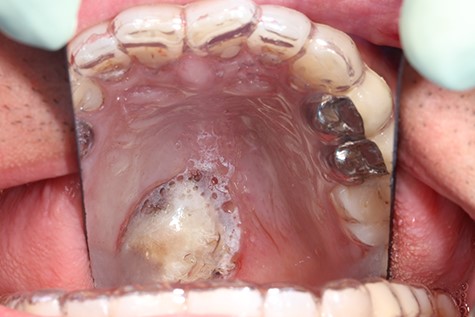

A 37-year-old patient with a recurrent, histologically confirmed steatocystoma of the palate was referred to our clinic. The patient’s medical history had already included two local removals of the tumor. Clinically, in the transition from hard to the soft palate, an asymptomatic, about 1 cm large, round, circumscribed and soft lesion was seen (Fig. 1). Magnetic resonance imaging was performed for further diagnosis and for assessment of spread and tissue infiltration of the finding. Here, a submucosal, 8 × 10 × 8 mm large tumor of delimited growth could be verified. It was T1 hypertense, T2 inhomogeneous partly hypointense, partly isointense with a significant signal drop in the T2 fat saturation (Fig. 2). There was no evidence of bony infiltration. The lesion was resected with a safety margin of 1–2 mm protecting the nerve and the greater palatine artery up to the palatal bone (Figs 3 and 4). As a secondary granulation of the defect was intended, the wound was first treated with a cellulose tamponade and tranexamic acid gel to prevent bleeding. An acrylic splint was then incorporated as a pressure bandage and wound protection (Fig. 5). The histopathological examination of the removed specimen showed a soft and glandular tissue covered with squamous epithelium with manifestations of a cystic, regressively changed epithelial lesion, which was compatible with the clinically known steatocystoma (Fig. 6). Follow-up examinations at 3-month intervals showed a good wound healing with complete restitution without evidence of recurrence after 1.5 years.

Clinical appearance of the tumor in the transition from hard to the soft palate on the left side of the mouth